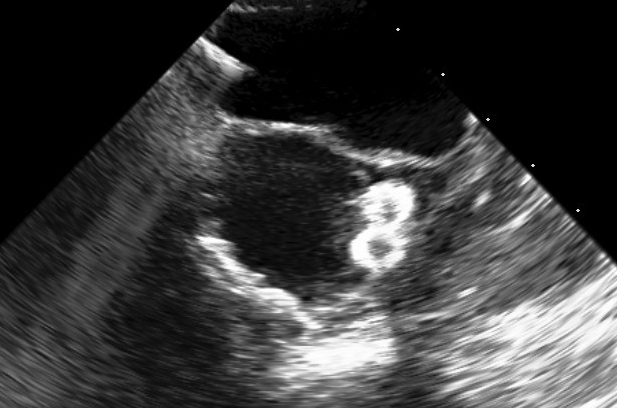

Final result showing the absence of any intra-prosthetic or paravalvular regurgitation. Final gradient was 15 mmHg. The patient recently completed 2-year follow-up: he is still asymptomatic with persistently good result at transthoracic echo.